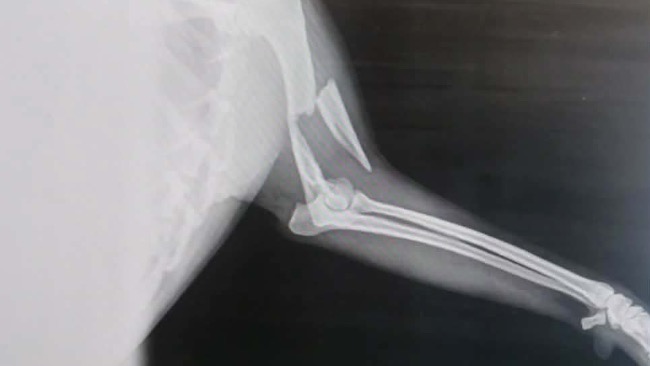

Marian to młody, cudowny psiak, który zamiast świątecznego spokoju dostał wypadek komunikacyjny. Trafił do nas połamany, poturbowany, z bólem, który trudno sobie wyobrazić.

Jego łapka… dosłownie wisi. Jest przerwana.

📌 Zaraz po świętach Marian będzie operowany.

Koszt samej operacji to 3500–3800 zł, ale to dopiero początek.

Przed nim rehabilitacja, leki i opieka pooperacyjna.

Łączne koszty szacujemy na około 4500 zł — a mogą jeszcze wzrosnąć.